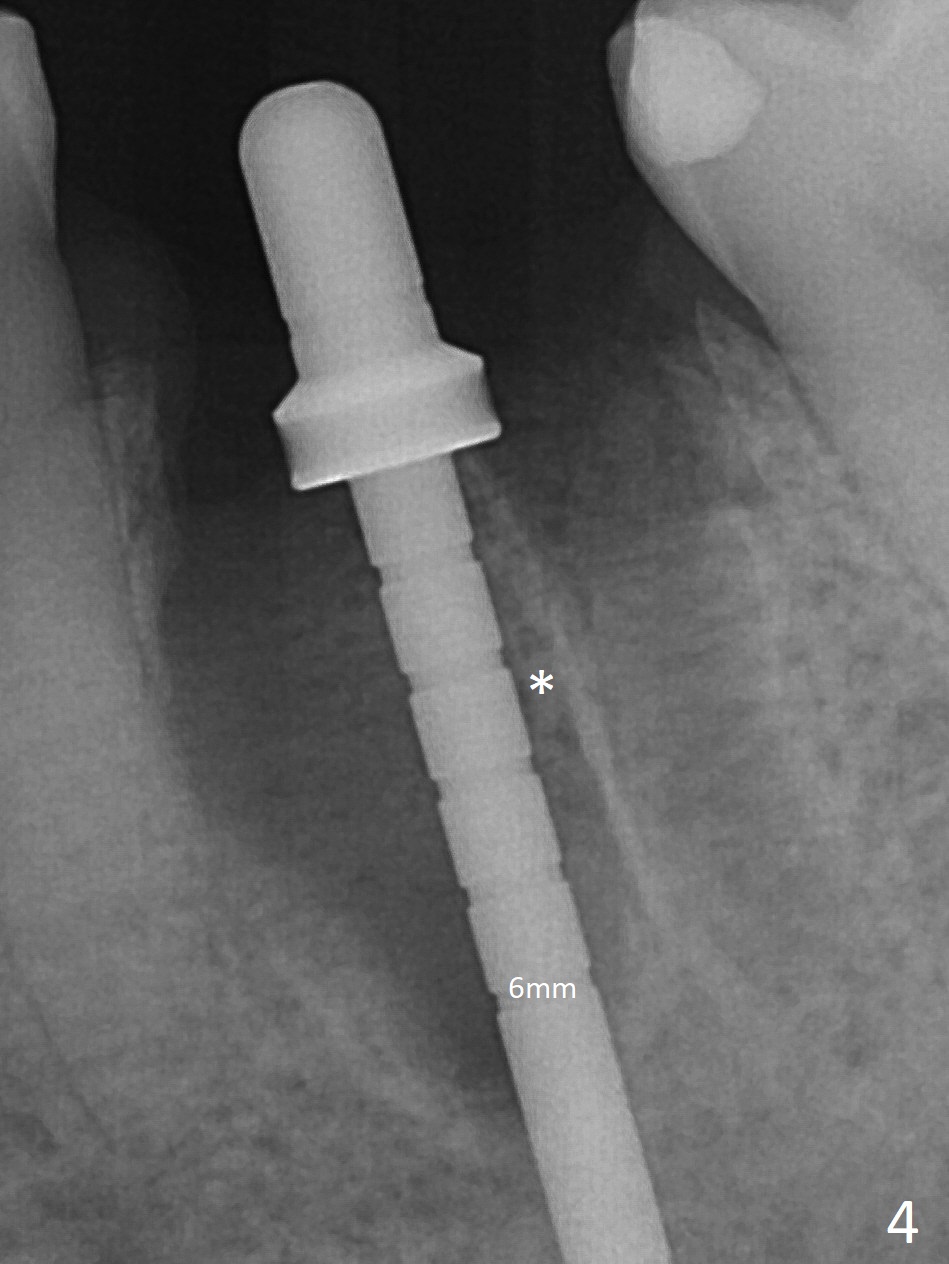

When the patient returns 9 months later, there is severe buccal gingival recession and abscess at #19 (Fig.1 *) with large mesial periradicular radiolucency (Fig.2 *).  The septum is thin and the buccal crest is low after extraction (Fig.3 * (mesial root vertical fracture)).  Osteotomy is initiated in the mesial socket immediately against the septum (Fig.4.5) with ~ 5 mm in the native bone.  Due to severe buccal plate resorption, a shorter implant is placed (Fig.6; 5x15 mm in stead of 18 mm).  There is at least 2 mm gap buccally for Vanilla Graft, which is also placed next to the implant and the neighboring root (Fig.7 *).  There is clearance from the Inferior Alveolar Canal (Fig.8 red dashed line).  Both the mesial and distal sockets heal 5.5 months postop (Fig.9), although the apical portion of the distal socket was not filled with allograft (Fig.7).  The implant was placed mesial.  The straight abutment (6.5x4(4) mm) (Fig.10) is changed to an angled one (5.5 x15 degrees 3 mm cuff (Fig.11)) before impression.  The implant is also placed buccally.  Therefore the implant position is far more important than its length.  The abutment is retightened 2.5 months post cementation, which is related to mesiobuccal placement of the implant (Fig.12).  An ideal trajectory is determined by drawing 2 horizontal lines (at crestal and apical levels: red lines in Fig.13), finding a central point of each line (vertical short line) and joining these 2 central points (Fig.14 pink line).  In fact the ideal osteotomy should have been established distal to the septum in this case.  Guided surgery may alleviate the issue.  The crown is not loose, but the patient feels that the implant tooth cannot sustain mastication.  In fact the screw is removed with hand driver (not wrench).  The abutment hex is rounded and worn.  A new 5.5x4(4) mm abutment is placed (without knowledge of previous use of an angled abutment) with mesial reduction to reduce undercut and buccodistal margin lowered to reduce gingival embrasure. It is that the straight abutment could decrease the chance of screw loosening.  Otherwise the implant has to be removed for better trajectory.